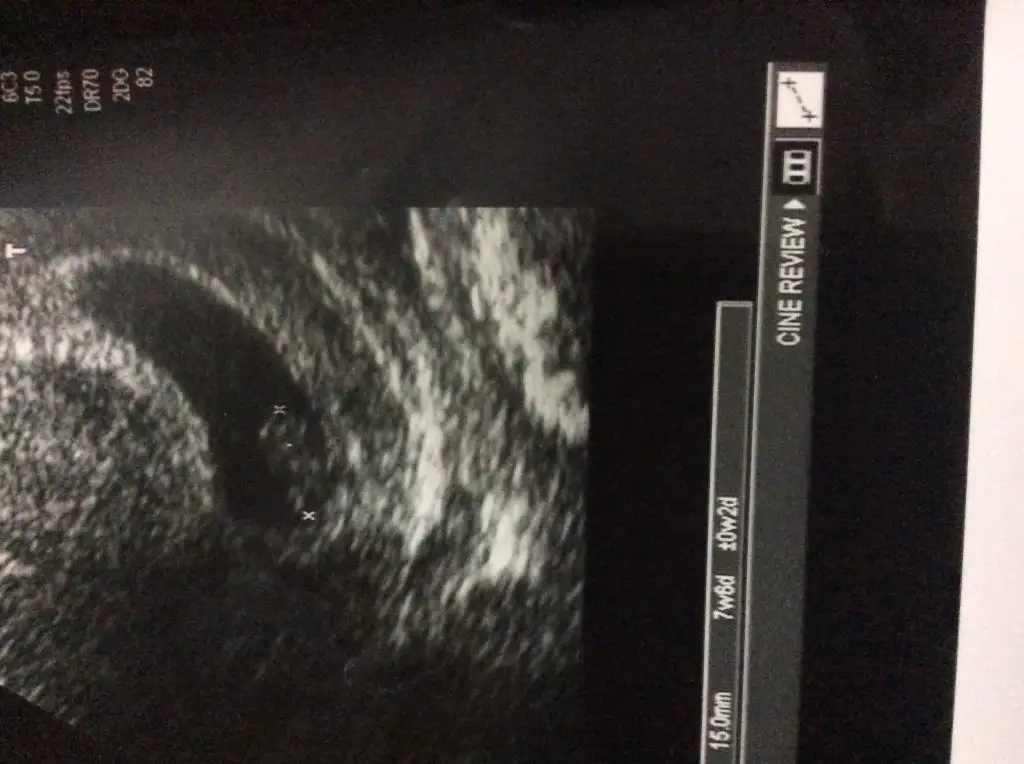

Sat 22nisan, yas 36 . Gecen sene bir düşükten sonra uzun denemelerden sonra bugün Allah'ın izniyle keseyi gördük ama Tiroid hastasıyım o oranlar biraz kaygılandırdı Dr. Hayırlısı ile inşallah hepimiz yavrularımızı sağlıkla kucağımıza alabiliriz.

Dün keseyi görmek için doktora gittim. Karından göremedi, vajinalden de bir an gördü, bir daha görüntü yakalayamadı. Ultrason görüntüleri tatmin edici değil, beta istiyorum dedi. Beta hcg bir haftada 415'ten 1134 e yükselmiş. Yani yükselme yetersiz. Gebelik yok demiyorum ama veriler çok olumlu değil. Kanaman ya da ağrın da yok. Pazartesini bekleyelim dedi.

kızlar sizce kese mm önemli mi .4.hafta mesela kaçtı kese boyutu benim 7.8 normal mi sizce bize kalp atışı için 3 hafta sonraya gün verdi.bugün 4+5 olduğumuzu düşünürsek 3 hafta sonra 7+5 oluyoruz.dr garantiye almak için dedi ama ben yine de daha erken olsa diyordum.sizin ne zaman duyuldu.

Benimki 4+4 te 6,8 5+4 te 2 cm olmuştu daha sonra gitmedim. Önemli olan bir sonraki kontrolünde kesenin büyüme hızı yani gelişimi demişti doktorum. kalp atışı içinde 7+3 te gidiyorum 2 haziranda inşallah